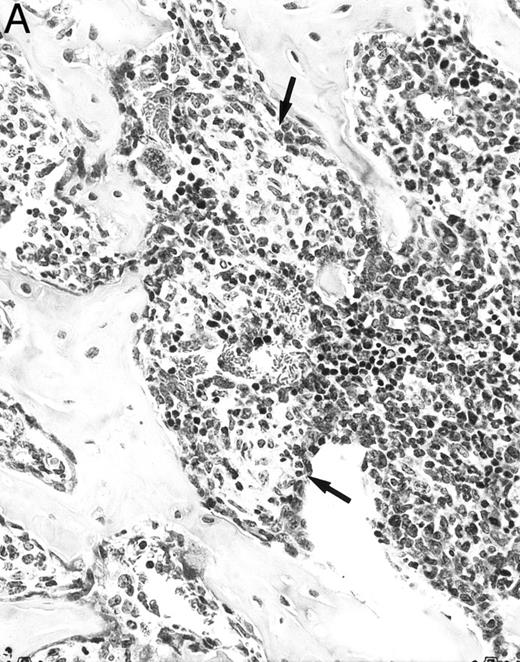

Histologic alterations occur in hematopoietic tissues of IFN-γ transgenic mice.Focal granulomatous lesions were seen in the bone marrow of many of the transgenic mice (Fig 4A) but not in control mice. These lesions were found to contain primarily Mac-2+ mononuclear cells (data not shown). In addition, the marrow cavities of IFN-γ transgenic mice contained residual degenerated cartilaginous masses in the metadiaphyseal (young) or diaphyseal (adult) parts primarily in long bones and ribs (Fig 4B). Moribund transgenic mice often had generalized or local secondary bacterial infectious lesions, including pyelonephritis, meningoencephalitis, endocarditis, bone marrow necrosis, arthritis, and uterine granulomas. Bacteria and bacterial colonies were often seen within the lesions.

Bone marrow alterations in IFN-γ transgenic mice. (A) Tibial bone marrow of a 3-month-old transgenic mouse showing granulomatous lesions (arrows) stained with H&E. The focal lesions were composed of clusters of histiocytes/macrophages (original magnification × 300; Bouin's fixed and paraffin-embedded section). (B) A rib of an 8-month-old transgenic mouse showing a cartilaginous mass in the marrow cavity attached to the cortical bone. Chondrocytes in the mass are degenerative. The mass is covered with a thin osseous layer. (Original magnification × 75; H&E; Bouin's fixed and paraffin-embedded section.)